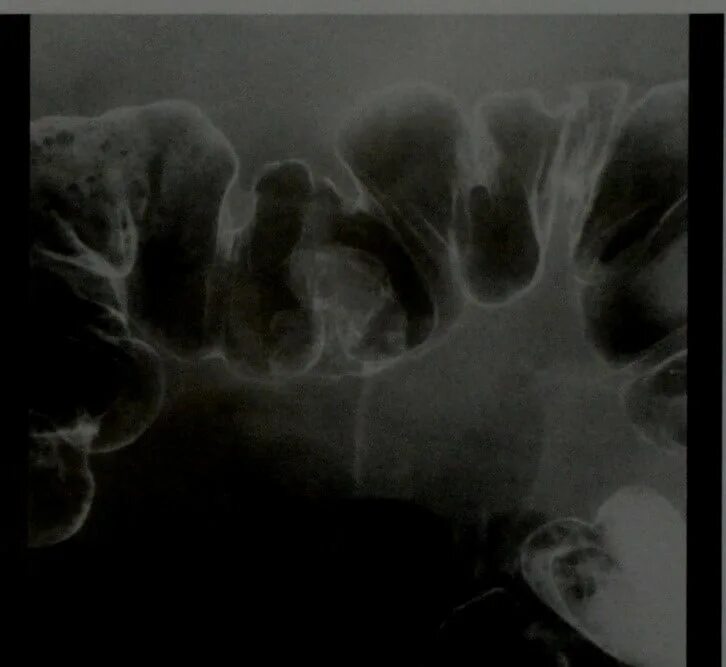

Полипы прямой кишки код по мкб 10